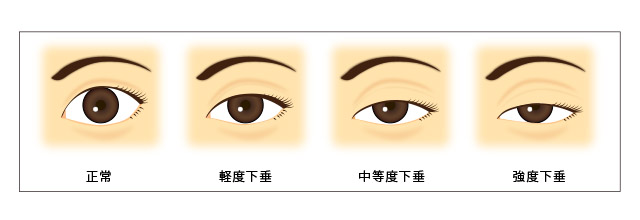

眼瞼下垂種手術のイラスト例